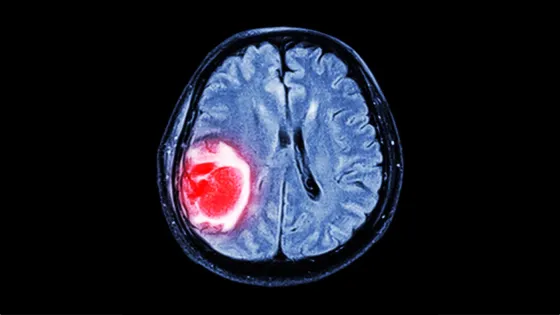

- Метастазы являются основной причиной смерти от рака и особенно опасны в головном мозге.

- Исследование выявило два белка, CD24 и CD47, которые помогают раковым клеткам избежать уничтожения микроглией.